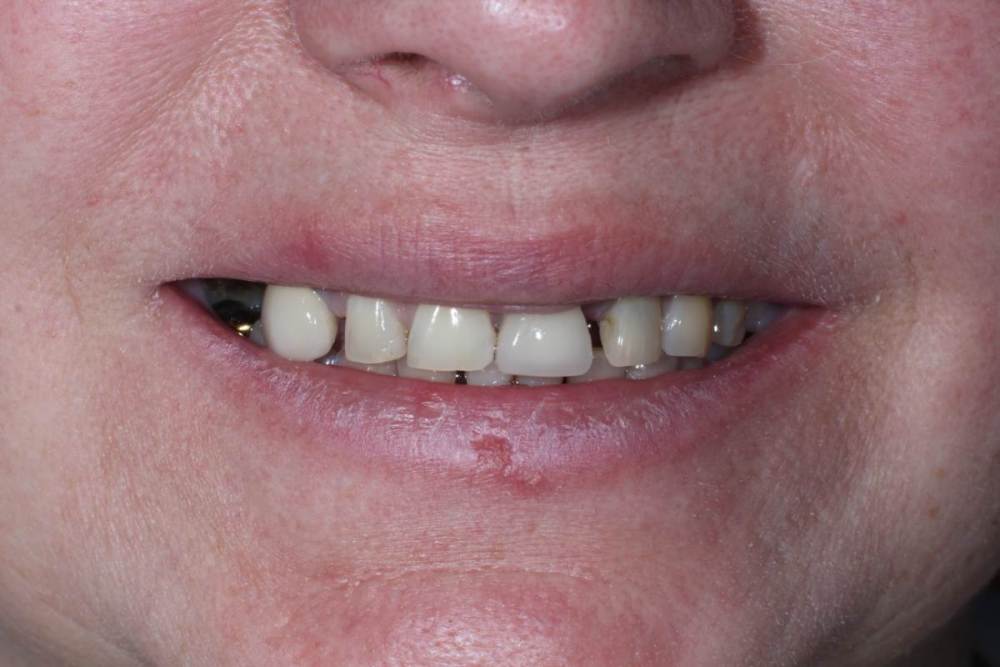

Улыбка до:

IMG_0634.thumb.jpg.5ffaa548d0888778b0f37eea7c1e219e.jpg